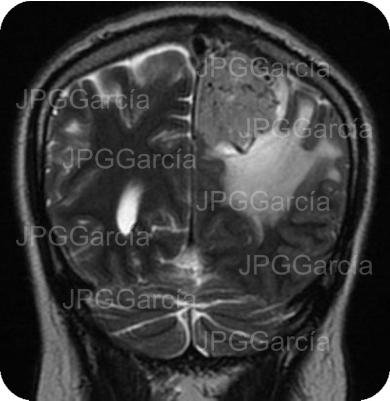

Tumor del plano esfenoidal clasificado por imagen como Meningioma visto a través de resonancia magnética cortes axial y coronal